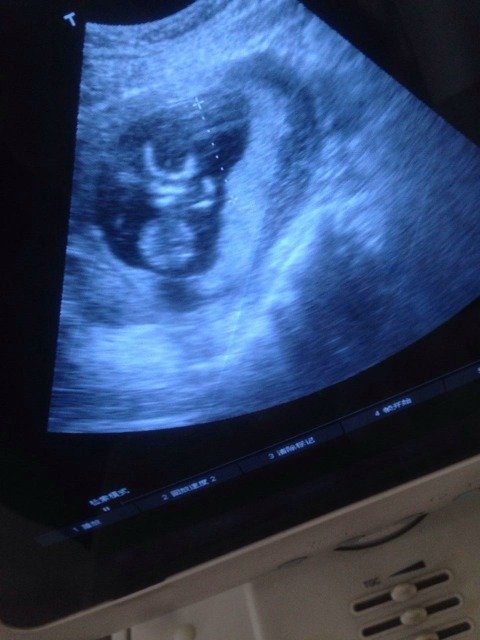

虽然检查了,说可能是男宝,但是还是好奇,有知道的帮我看看这是男宝女宝 虽然检查了,说可能是男宝,但是还是好奇,有知道的帮我看看这是男宝女宝 点击展开 Mylovez 2015-03-03 12:56 为您推荐: 其他回答 看不出,我用试纸测的男宝生的也是男宝 t lo w x 2015-03-03 13:50 不知道。。。。 you belong with me,, 2015-03-03 13:25 太可爱了恭喜你 含蓄, 2015-03-03 13:17 看不出来的 飞花逐月 2015-03-03 13:08 你好,从B超单子上是没法儿看出是男孩儿还是女孩儿的,只有正好看到外生殖器才能确定,既然说了是男孩儿一般就错不了的 żе㻵2011 2015-03-03 13:02 加载更多 相关问题 嘿嘿,有没有会看的帮我看看男宝女宝啊,自己的不管什么宝都爱只是好奇而已 有经验的宝妈帮我看看这肚型是男宝女宝(⊙o⊙)哇,超好奇 四维归来,宝宝不配合,不是用手捂着脸就是两只脚敲脸上,来来回回检查了三次,还好结果是好的 有会看男女的宝妈吗?帮我看看,纯粹好奇 男宝女宝都爱